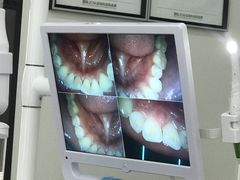

• 牙博士口腔品牌连锁(杨浦店)

• -牙博士口腔品牌连锁(杨浦店)

苹果VS丫头 | 21-01-27